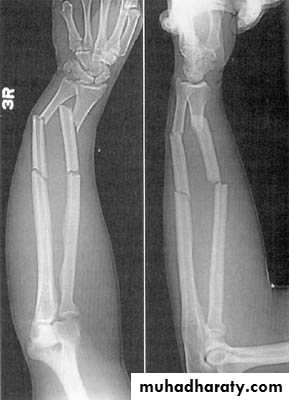

15Special types in children

Green-stick # : one cortex fractured & the opposite is compressed

Buckle fracure

Plastic deformation